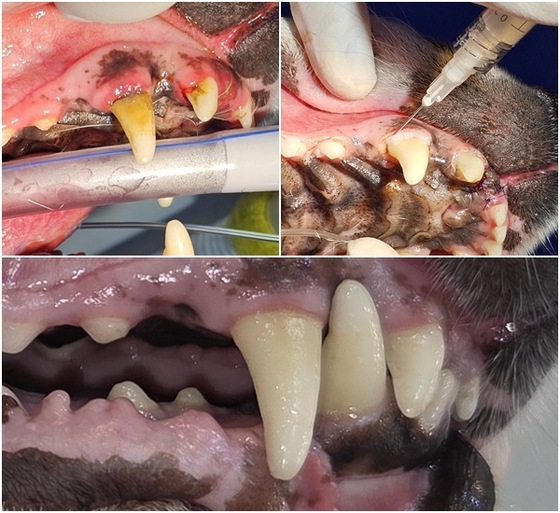

이 과정에서 사용된 애니씰 덴탈콜라겐은 치주 조직 회복을 돕는 보조재다. 라라동물의료원에서는 치과 치료 시 기본 프로토콜로 활용되고 있다.

그는 "치주염 환자는 발치 이후 회복이 무엇보다 중요한데, 덴탈콜라겐을 사용하면 조직 안정과 회복 속도에서 차이를 체감할 수 있다"며 "짧은 기간 안에 잇몸이 빠르게 안정되는 사례를 반복적으로 확인하고 있다"고 말했다.

송곳니 부위 치주염이 심해(상단 왼쪽) 스케일링 시 애니씰 덴탈콜라겐을 도포하는 모습(상단 오른쪽)과 치료 후 회복된 모습(아래) (병원 제공) © 뉴스1